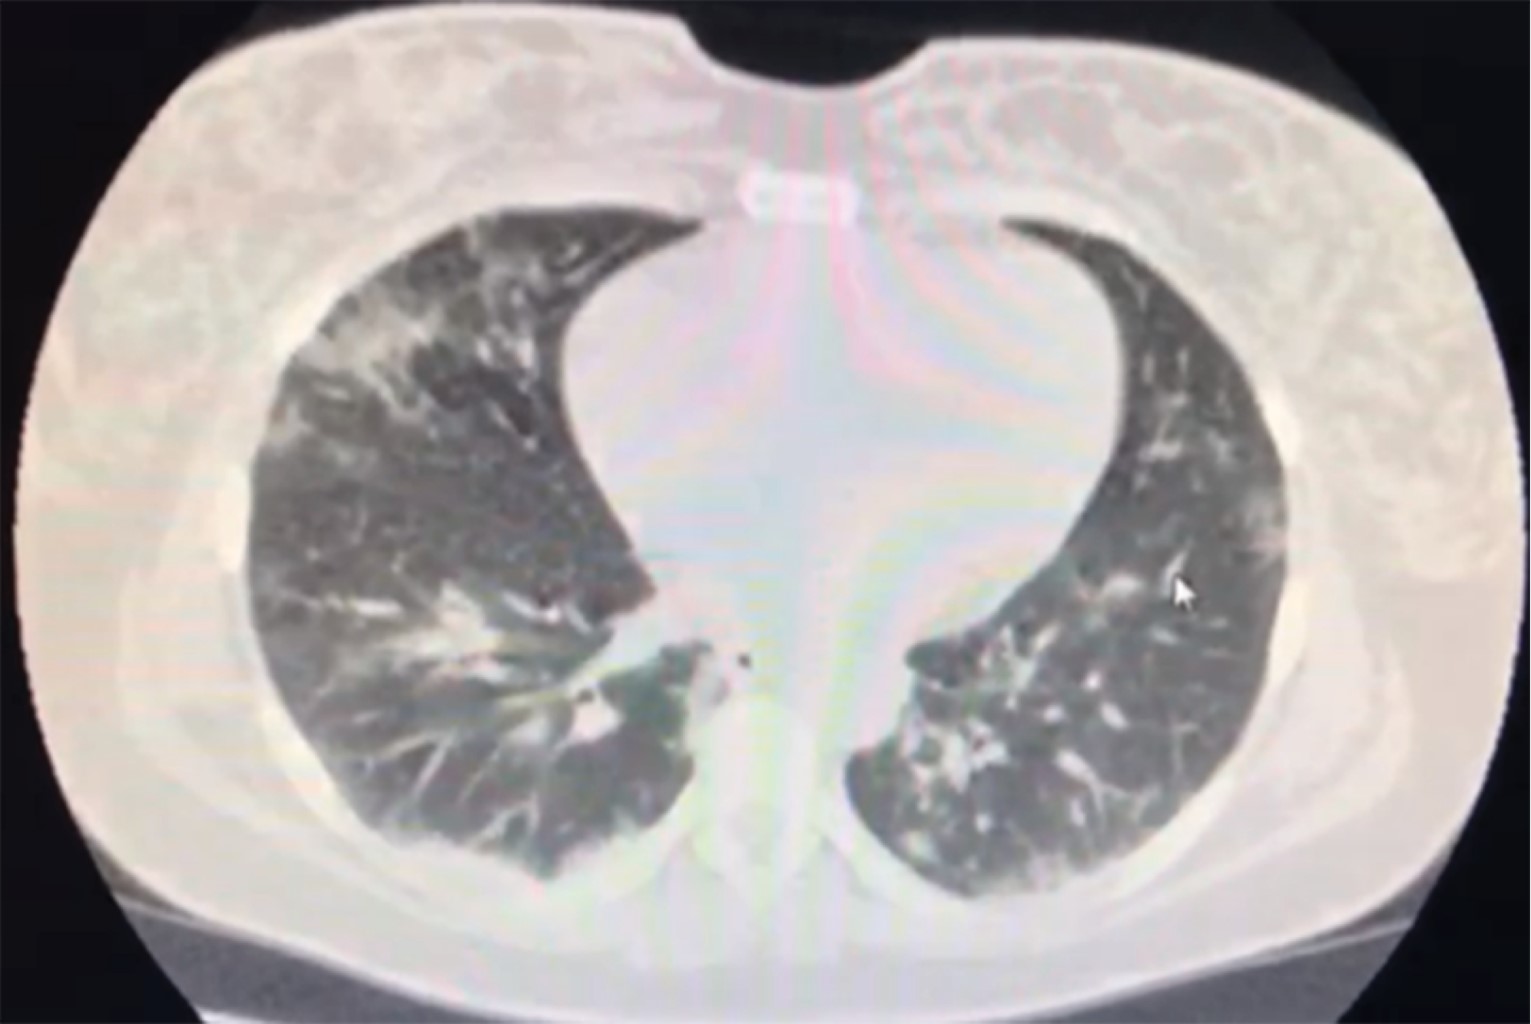

Figure 3